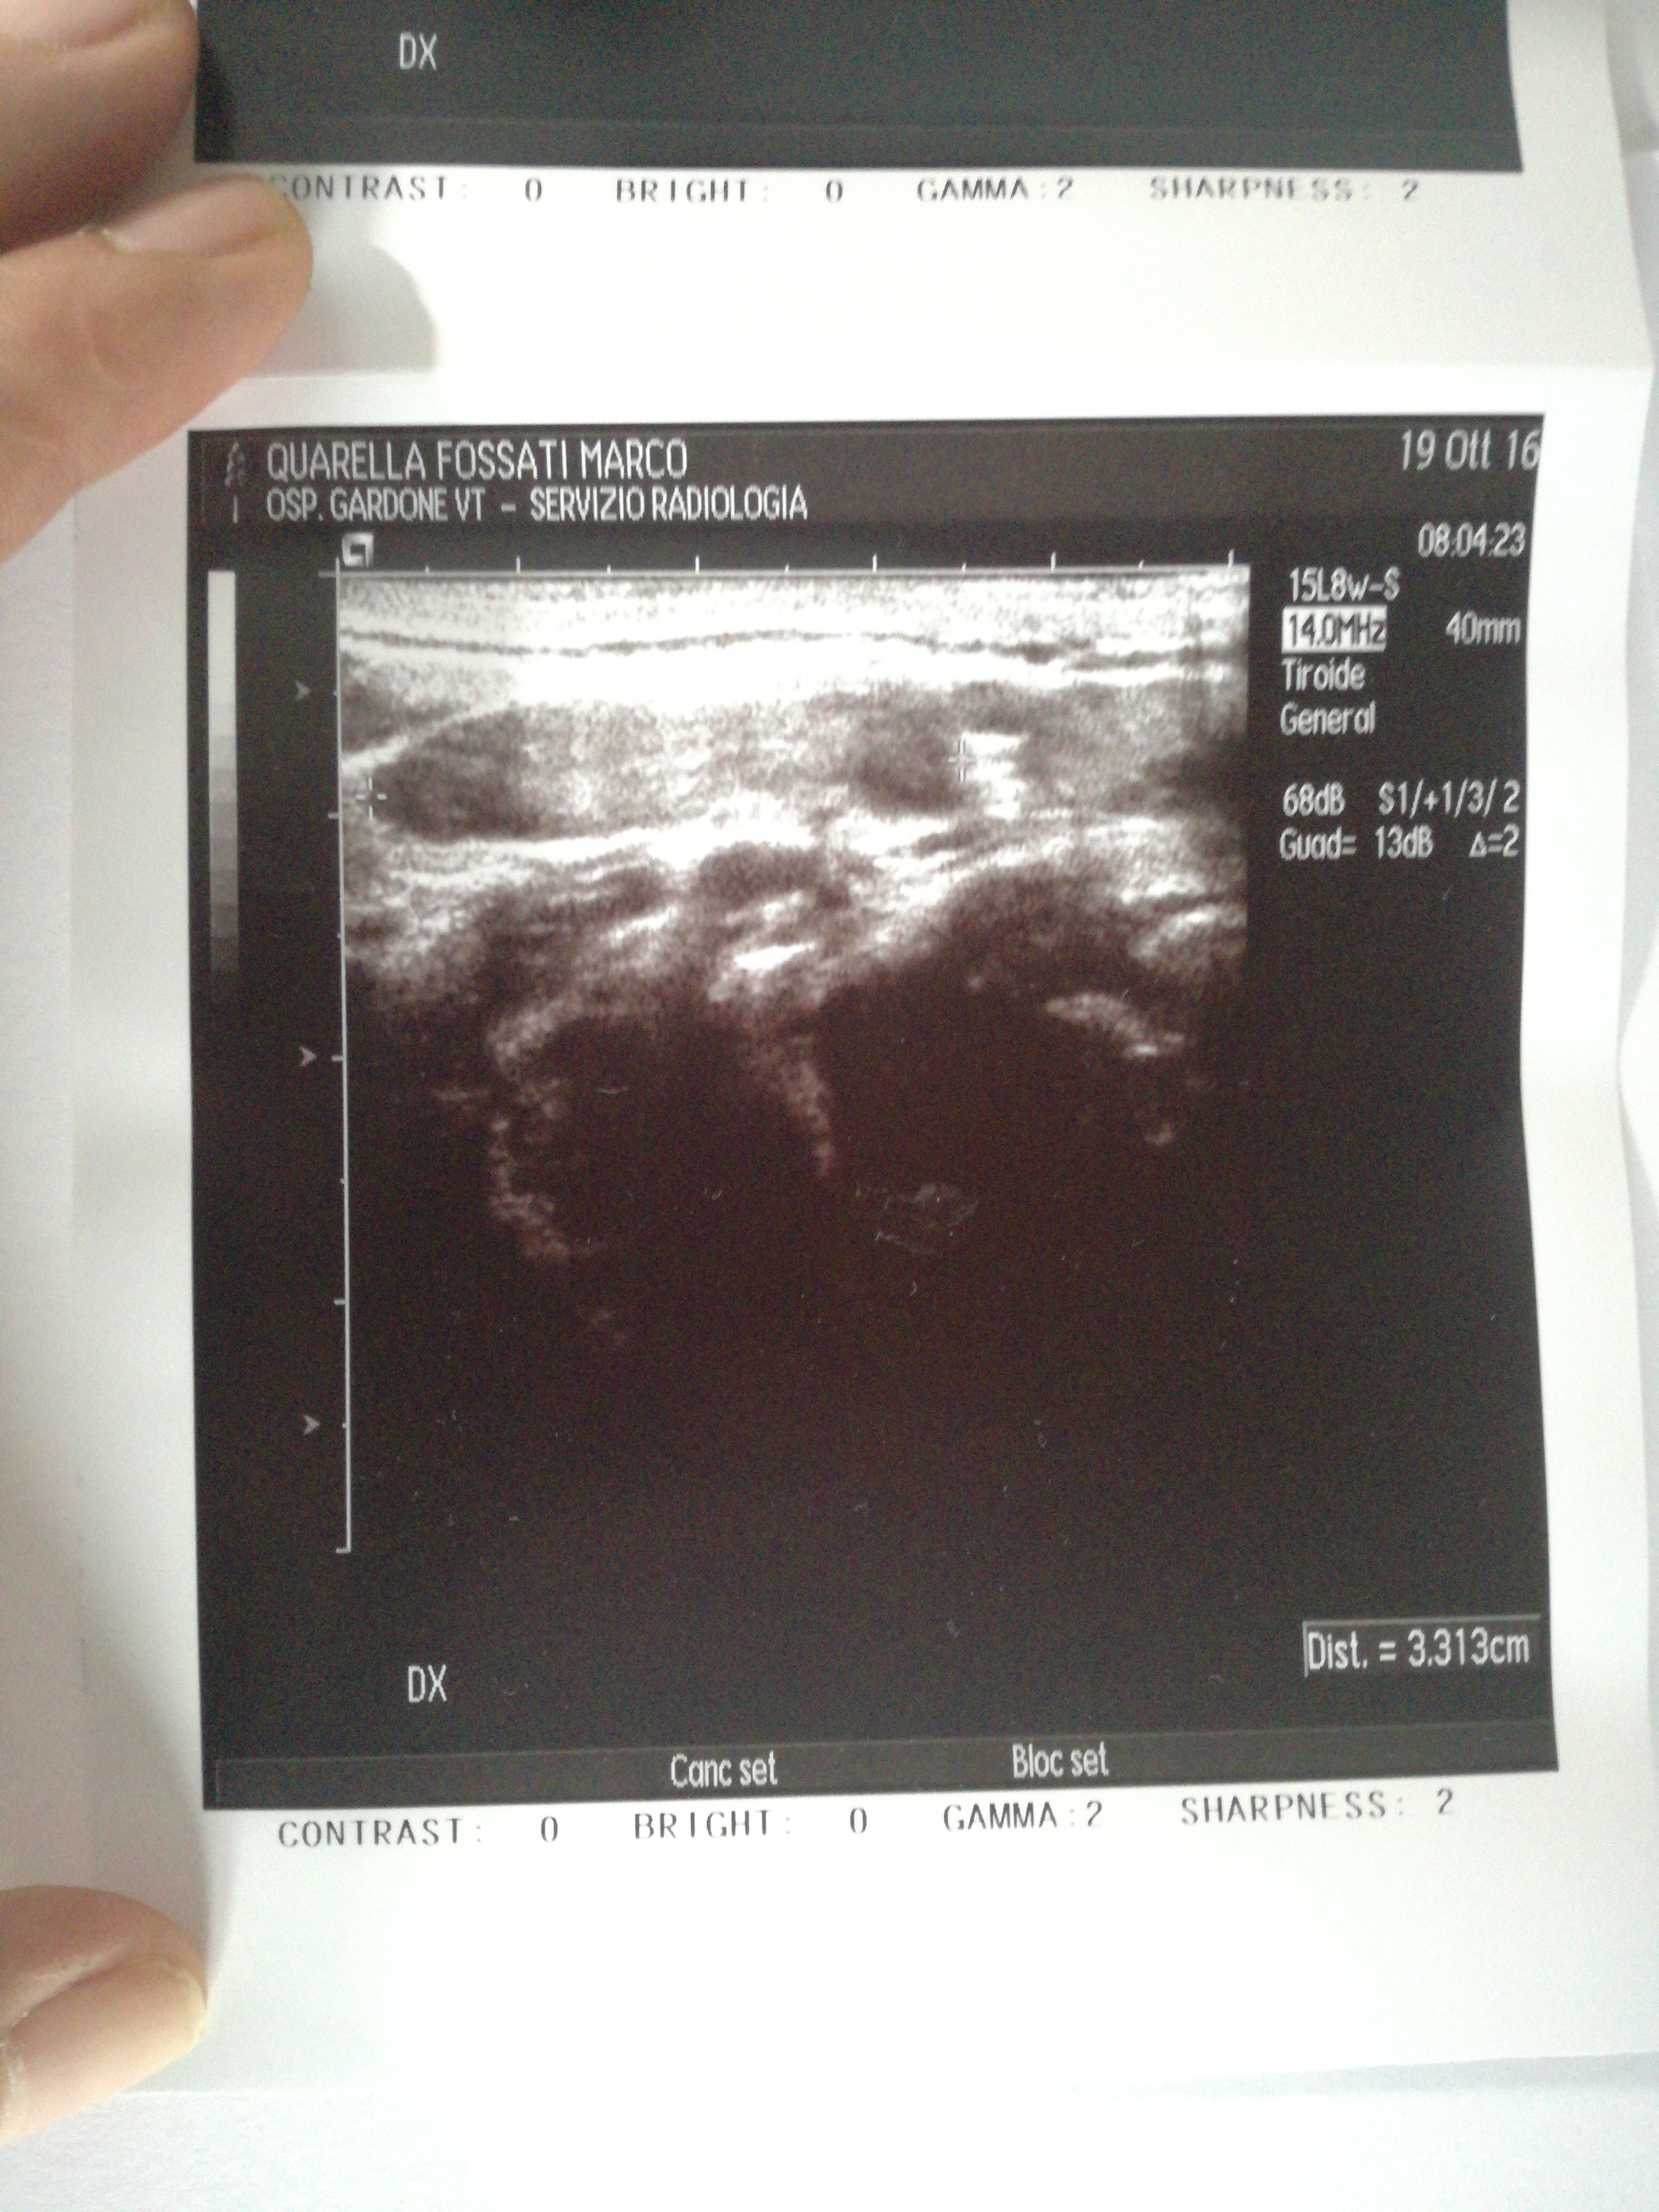

In sede laterocervicale bilaterale alcuni linfonodi con caratteristiche ecografiche immunoreattive, con diametro massimo di 2 cm in sede jugo-digastica destra. Anche la tumefazione clinicamente apprezzabile in regione nucale destra è sostenuta da piccolo linfonodo immuno-reattivo superficiale.

Guardando le otto immagini dell'ecografia (5 DX e 3 SN) solo in due immagini si vendono dei linfonodi contrassegnati agli estremi da due croci e in basso a destra dell' immagine leggo dist. = 1.10 cm in un'immagine e nell'altra la misura è dist. = 3.313 cm.

Credo che la distanza sia il diametro massimo, ma allora come mai nel referto c'è scritto "diametro massimo 2 cm", ma nell' immagine c'è scritto 3.313 cm?